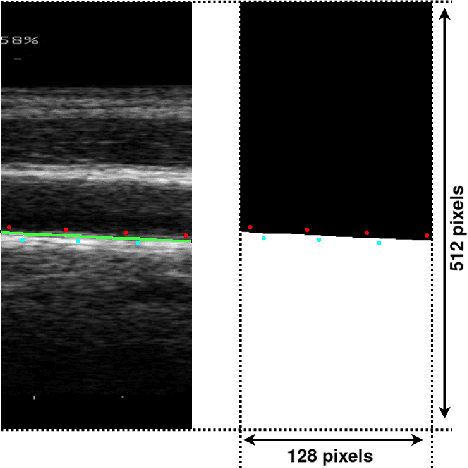

Abstract:Purpose: The motion of the common carotid artery tissue layers along the vessel axis during the cardiac cycle, observed in ultrasound imaging, is associated with the presence of established cardiovascular risk factors. However, the vast majority of the methods are based on the tracking of a single point, thus failing to capture the overall motion of the entire arterial wall. The aim of this work is to introduce a motion tracking framework able to simultaneously extract the trajectory of a large collection of points spanning the entire exploitable width of the image. Method: The longitudinal motion, which is the main focus of the present work, is determined in two steps. First, a series of independent block matching operations are carried out for all the tracked points. Then, an original dynamic-programming approach is exploited to regularize the collection of similarity maps and estimate the globally optimal motion over the entire vessel wall. Sixty-two atherosclerotic participants at high cardiovascular risk were involved in this study. Results: A dense displacement field, describing the longitudinal motion of the carotid far wall over time, was extracted. For each cine-loop, the method was evaluated against manual reference tracings performed on three local points, with an average absolute error of 150+/-163 um. A strong correlation was found between motion inhomogeneity and the presence of coronary artery disease (beta-coefficient=0.586, p=0.003). Conclusions: To the best of our knowledge, this is the first time that a method is specifically proposed to assess the dense motion field of the carotid far wall. This approach has potential to evaluate the (in)homogeneity of the wall dynamics. The proposed method has promising performances to improve the analysis of arterial longitudinal motion and the understanding of the underlying patho-physiological parameters.